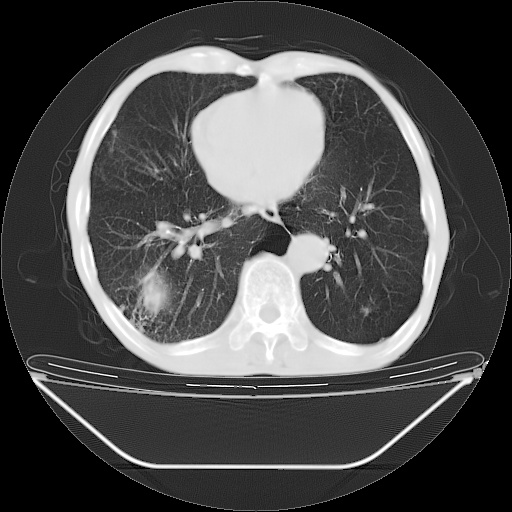

以下是引用随光逐影在2008-8-25 22:03:00的发言:[br]1)考虑右肺下叶周围性肺癌并肺内转移,腰椎附件转移。2)左上肺结核(结核球形成)。3)双肺肺气肿(多发肺大泡形成)。4)双肺门区及纵隔内多发淋巴结钙化。